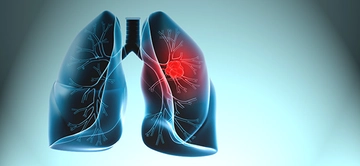

Bu sonuç, genellikle hastanın akciğer sağlığının iyi olduğunu ve herhangi bir ciddi patoloji olmadığını gösterir. Ancak, bu sonuçlar her zaman kesin bir tanı anlamına gelmez; doktorun klinik değerlendirmesi ve hastanın genel sağlık durumu da göz önünde bulundurulmalıdır. Temiz Akciğer Tomografisinin ÖnemiTemiz akciğer tomografisi sonucu, özellikle kronik akciğer hastalığı, kanser riski veya enfeksiyon öyküsü bulunan hastalar için büyük bir rahatlık kaynağıdır. Bu durum, hastaların tedavi süreçlerine olumlu yönde katkı sağlar ve gereksiz endişeleri azaltır. Ayrıca, temiz bir tomografi sonucu, sağlık profesyonellerine hastanın durumu hakkında daha fazla bilgi verir ve gelecekteki muayene ve tedavi planlamalarına yardımcı olur. SonuçTemiz akciğer tomografisi, akciğer sağlığının iyi olduğunu gösteren önemli bir bulgudur. Ancak, bu sonucun değerlendirilmesi için mutlaka bir sağlık profesyoneliyle görüşülmesi gerektiği unutulmamalıdır. Her durumda, kişinin genel sağlık durumu, belirtiler ve diğer tetkiklerin sonuçları birlikte ele alınmalıdır. Sağlıklı bir yaşam tarzı, düzenli kontroller ve zamanında yapılan tetkikler, akciğer sağlığının korunmasında önemli rol oynamaktadır. |